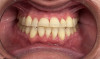

In addition, teeth affected by attrition will require restoration, and clear aligner therapy additionally provides the necessary tooth alignment to facilitate the fabrication of restorations (Figure 3 and Figure 4).

Fig 3. After orthodontic treatment with clear aligner therapy in the same patient shown in Fig 1 and Fig 2, restorative treatment of the teeth affected by attrition was

performed. This photograph shows a post-treatment retracted view of final porcelain-fused zirconia crowns on teeth Nos. 5 through 12.

Figure 3

Fig 4. Post-treatment retracted left

lateral view of the final porcelain-fused zirconia crowns in this same patient.

Figure 4